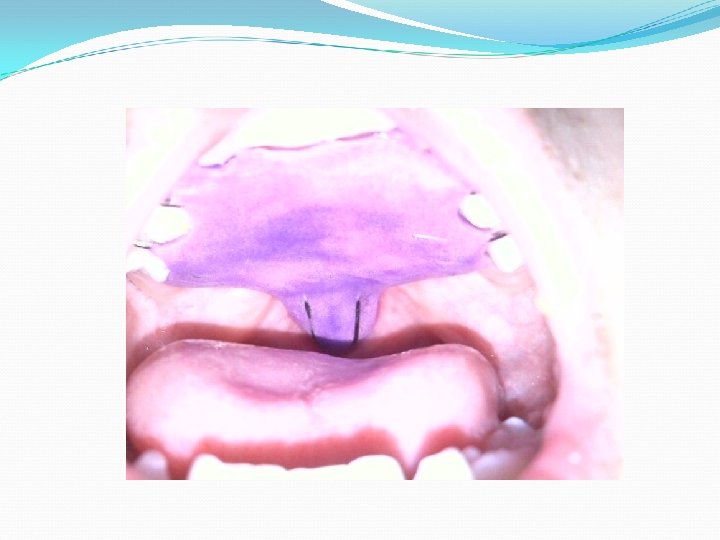

KEY POINTS: Rule out obvious structural issues such as a palatal fistula that does not allow for a build up of oral pressure even in the presence of a functional soft palate; may need obturator to cover fistula in the hard palate.

Fistula